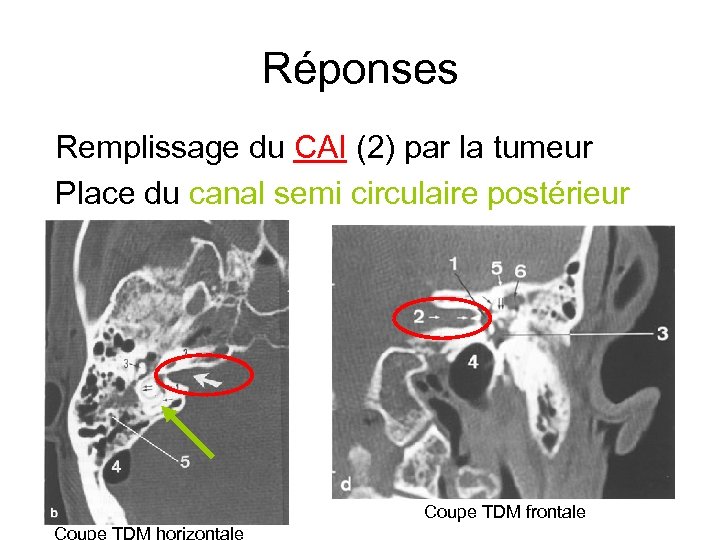

Réponses Remplissage du CAI (2) par la tumeur Place du canal semi circulaire postérieur Coupe TDM frontale Coupe TDM horizontale

Réponses Remplissage du CAI (2) par la tumeur Place du canal semi circulaire postérieur Coupe TDM frontale Coupe TDM horizontale